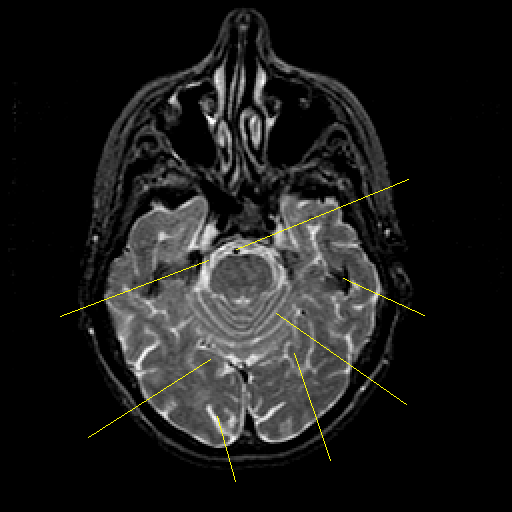

T2-weighted structural MR: Slice 17

Slice 17

Pointers

Labeled